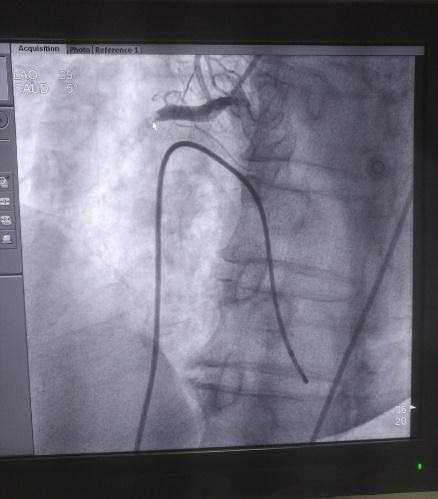

| Hình ảnh huyết khối gây tắc cụt động mạch vành phải từ đoạn I. Ảnh: Bệnh viện Đa khoa Đức Giang |

Trước tình hình đó, các bác sỹ đã thảo luận nhanh và đưa đến chẩn đoán bệnh nhân bị ngừng tuần hoàn do nhồi máu cơ tim cấp, cần can thiệp cấp cứu. Sau 45 phút, ca can thiệp thành công, huyết áp bệnh nhân được kiểm soát tốt.